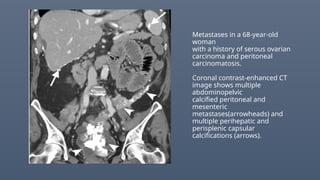

Metastases in a 68-year-old

woman

with a history of serous ovarian

carcinoma and peritoneal

carcinomatosis.

Coronal contrast-enhanced CT

image shows multiple

abdominopelvic

calcified peritoneal and

mesenteric

metastases(arrowheads) and

multiple perihepatic and

perisplenic capsular

calcifications (arrows).